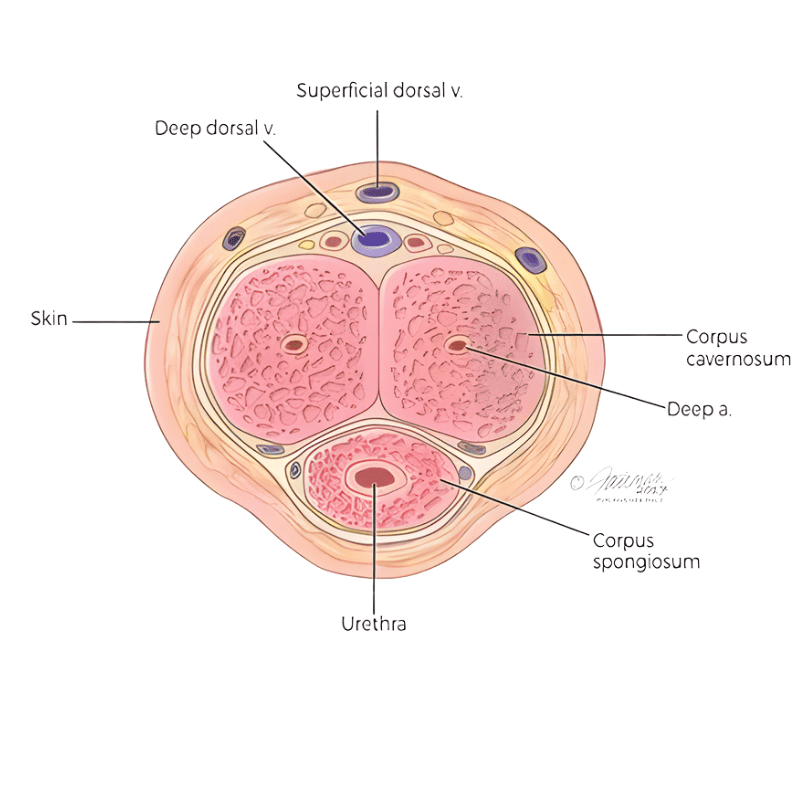

Melancarkan Darah Mikro Tisu Zakar

Sistem saluran darah halus yang bertindak sebagai pengisi, pengedar, dan pengering untuk memenuhi zakar dengan darah dan memerangkapnya di dalam, lalu menghasilkan ereksi.

Mengekalkan Keupayaan Mr. P

Krim menyerap ke rangkaian saluran mikro dan memenuhi semua ruang kosong dalam span tisu. Apabila span dipenuhi darah, ia mengembang seperti belon.